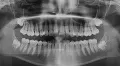

Опишите, пожалуйста, панорамный снимок. Пол женский, 30 лет. Беспокоят передние резцы - 11 и 21 и 26 остро реагирует только на горячее. Может ещё есть проблемы, воспаления, кисты?

• Снимок очень плохого качества. Зубы 1.1, 2.6,

4.6 - депульпированы. В зубе 1.1 либо не до конца запломбированы корневые каналы, либо рассосался материал. По остальным ничего не видно на верхушках корней, нужен более информативный снимок.